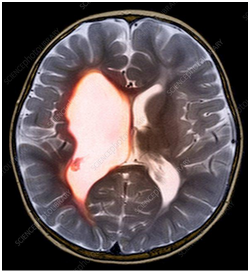

C) Brain Scans: These help doctors understand what kind of brain damage may have occurred.